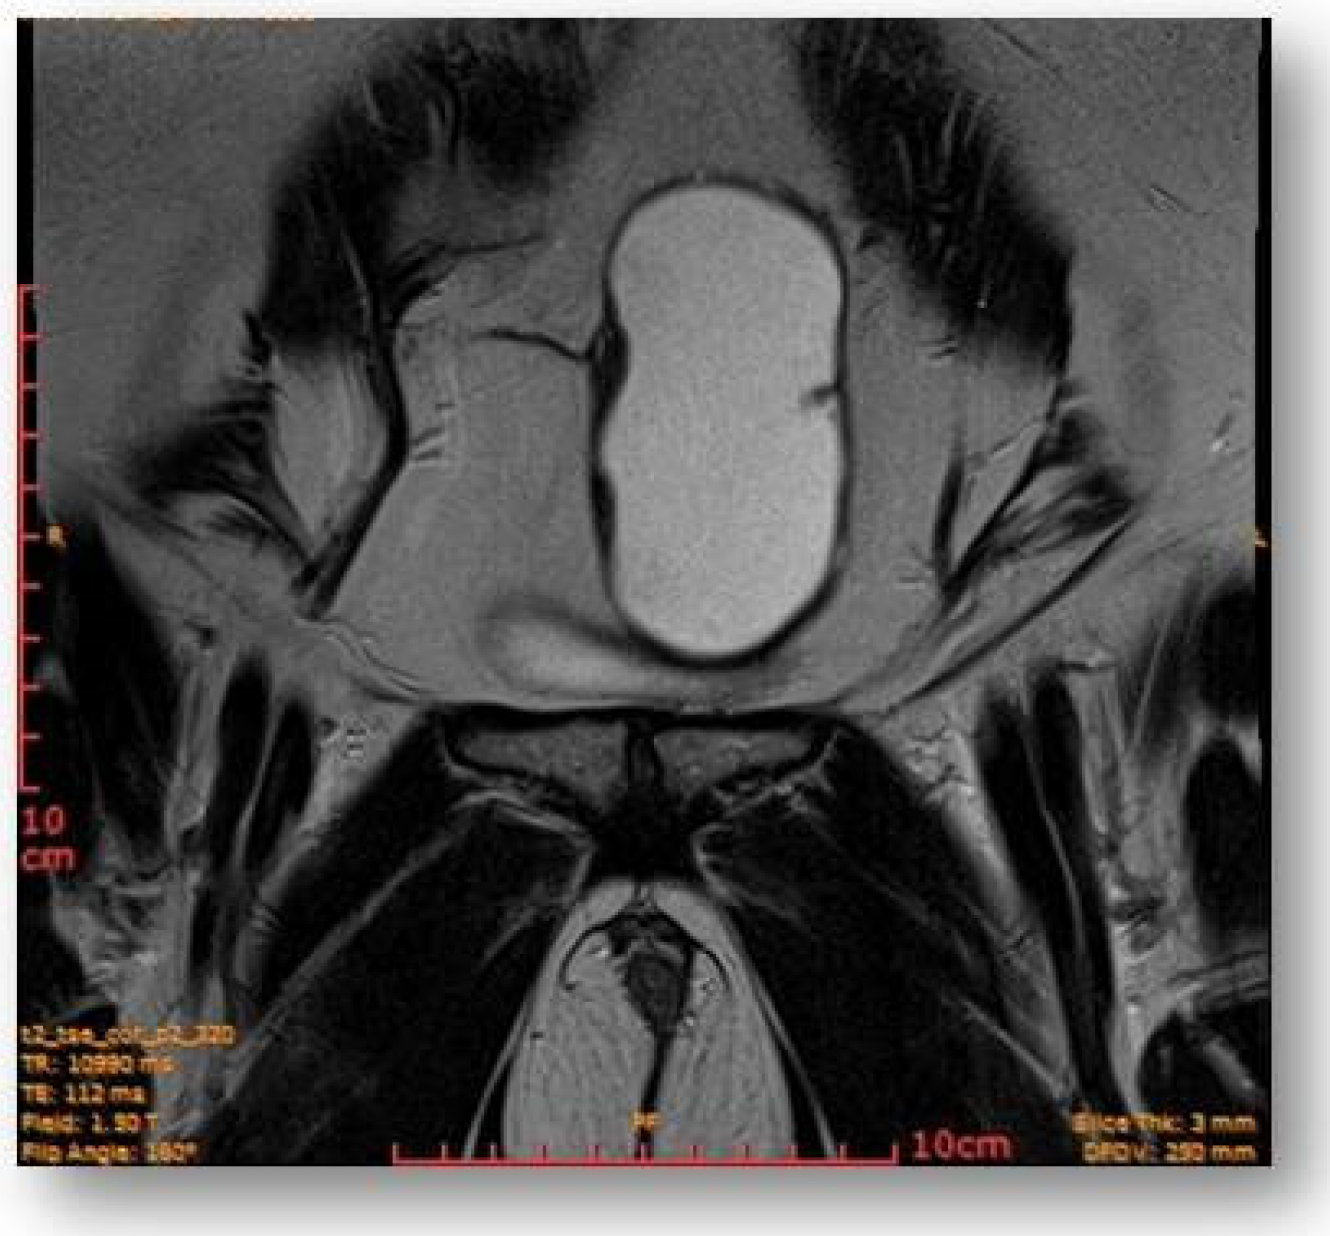

The rectal ampulla did not show suspicious tumor masses. Several infracentimetric pelvic lymph nodes, without specific character, were noted, as well as a minimal plate of intrapelvic fluid with a millimeter thickness. No notable collections in the pelvic recesses. No suspicious focal bone lesions were evident in the pelvis on the acquired images. Diastasis of the rectus abdominis muscles in the pelvic region (distance of about 30–35 mm) could be observed (Figure 7 and Figure 8).

Figure 7.

Ovoid cystic lesion proteinaceous fluid content and mildly irregular wall thickness up to ~4–5 mm.

Figure 8.

Ovoid cystic lesion in the left part of the uterus.